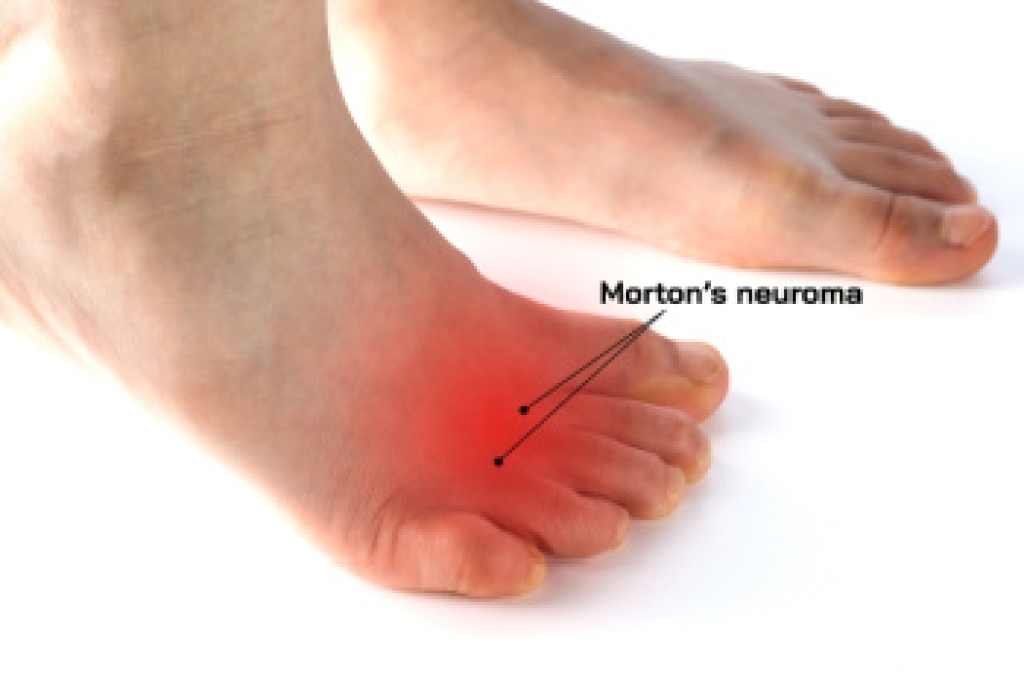

Gout is a form of arthritis that is characterized by sudden, severe attacks of pain, redness, and tenderness in the joints. The condition usually affects the joint at the base of the big toe. A gout attack can occur at any random time, such as the middle of the night while you are asleep.

- Intense Joint Pain - Usually around the large joint of your big toe, and it most severe within the first four to twelve hours

- Inflammation and Redness -Affected joints may become swollen, tender, warm and red